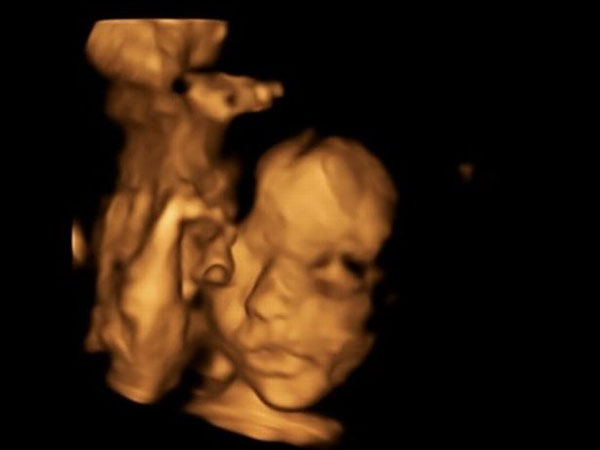

26 வயது பெண்மணி ஒருவர் கருவுற்றிருந்தார். அந்த சந்தோஷத்தை முழுமையாக அனுபவிப்பதற்குள் அவருக்கு ஒரு துயரமான செய்தி காத்திருந்தது. அதவது கருவில் உள்ள குழந்தைக்கு ஸ்பைனா பிஃபிடா என்னும் பாதிப்பு இருப்பதை மருத்துவர்கள் கண்டறிந்தனர். ஸ்பைனா பிஃபிடா என்பது முதுகு தண்டுவடத்தை சுற்றியுள்ள முதுகெலும்பு மற்றும் சவ்வுகளின் முழுமை பெறாத ஒரு பிறப்புக் குறைபாடாகும்.

கருக்கலைப்பை பெற்றோர் ஏற்றுக் கொள்ளாத நிலையில், மருத்துவர்கள் கருப்பை அறுவை சிகிச்சை என்னும் புதிய சிகிச்சையைப் பற்றி கூறினர். இந்த வகை சிகிச்சையில் குழந்தை பிறப்பதற்கு முன்னரே, குழந்தையின் பிரச்னையை சரி செய்வது என்று கூறினார். அதாவது, குழந்தையை தாயின் கருப்பையில் இருந்து வெளியில் எடுத்து, அந்த குழந்தையின் முதுகுத்தண்டு பிரச்னையை சரி செய்து, மீண்டு தாயின் கருவில் வைப்பது தான் இந்த சிகிச்சை. இந்த சிகிச்சை மூலம் குழந்தை சாராசரி வாழ்க்கையை வாழ இயலும்.